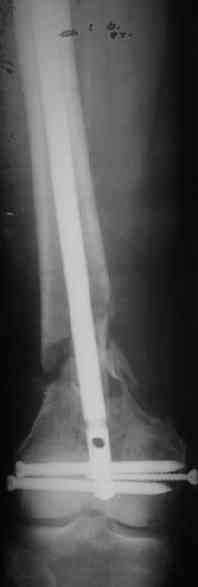

Удалили ластину без проблем. Выявилась значительная подвижность. В этих условиях сразу пропала мотивация к постепенной коррекции аппаратом. Попробовал восстановить длину, введя между отломками spreader. Отчасти удалось. Тогда защили рану, наложили спицевой дистрактор (2 спицы в дистальный отдел и 1 вверху). после этого был убран и спонгиозный винт. И сделали антгерадное штифтование, как говорится, "по принятой в

клинике методике".

Дополнительные доступы для введения гвоздя и проксимальных винтов понадобились, но они маленькие, по 1 см. Нижние винты ввели прямо между швами. Суставы дополнительно не травмировали, и даже ввели гвоздь не через f. piriformis, а через большой вертел.

Длину восстановили, возможно, даже с изьбытком, ну да динамизируем пораньше. Введенные в овальное отверстие дистальые винты имеют угловую стабильность. Снимки приложены. Заранее спасибо за критику и комментарии.